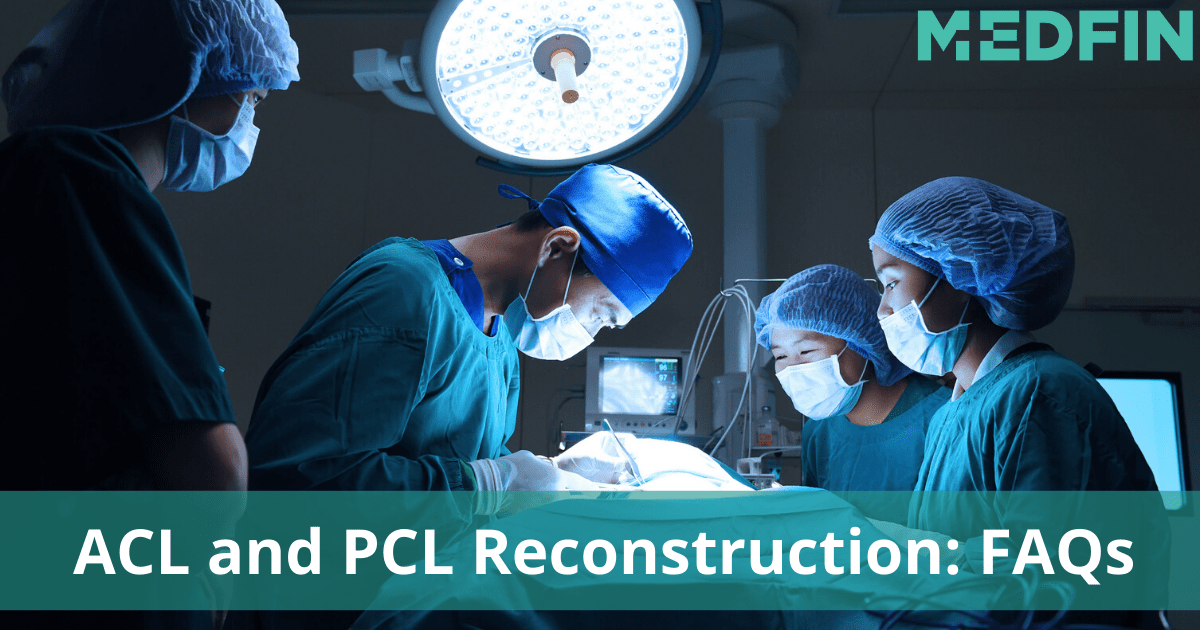

ACL reconstruction or PCL reconstruction usually takes a lot of patience, supervision by the doctor, physiotherapy and support…